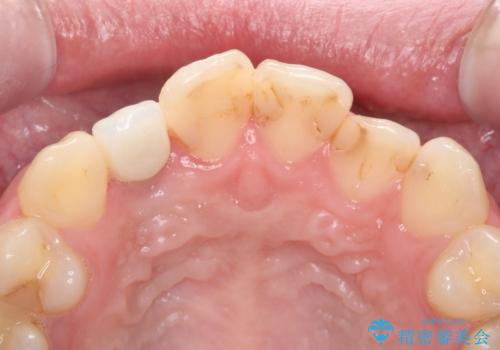

- 虫歯の治療を繰り返した前歯の見た目の改善を求めて来院されました。

大きく詰められたコンポジットレジンと虫歯の再発が見られ、経年劣化により審美性も損なわれていました。

前歯のコンポジットレジン修復は、経年劣化し虫歯の再発しやすい素材なので定期的なX線検査が推奨されます。